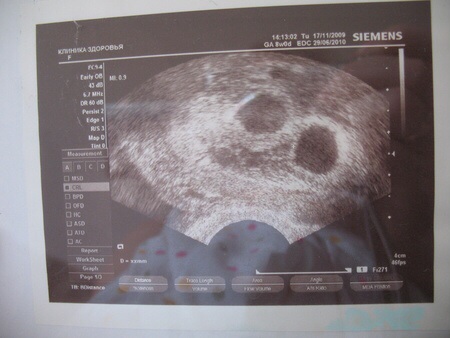

УЗИ двухплодной беременности на 5 неделе: Подборка изображений

Раздел: Калейдоскоп образов